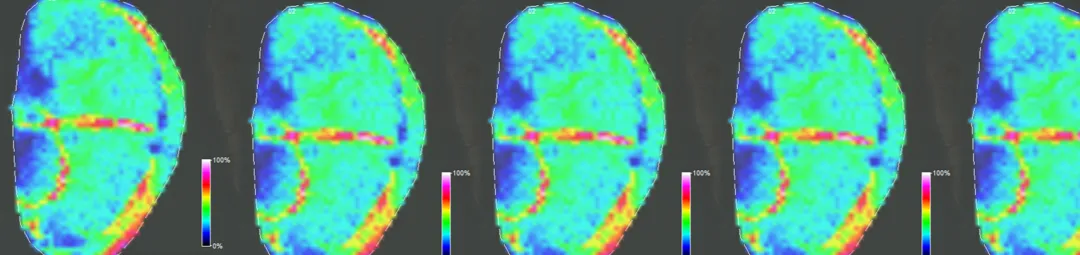

mass spec images of kidney tissue

We use matrix assisted laser desorption/ionisation mass spectrometry imaging (MALDI-MSI) for the generation of intensity and distribution maps of aldosterone and glucocorticoids on kidney tissue sections.